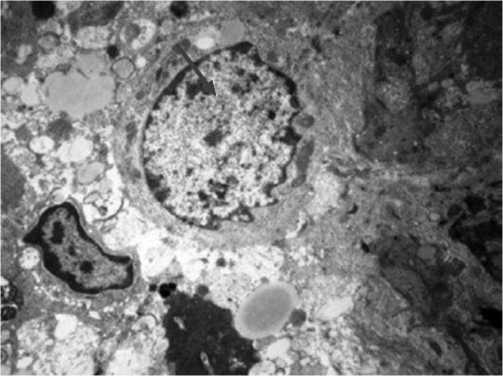

Рис. 2. Криорегенерат из туннеля после трехсекундного криовоздействия. Полутонкий срез. Окраска – толуидиновый синий. Увеличение х60.

картина неоостеогенеза, демонстрирующая активную кальцификацию регенерата и типичные признаки активного неоостеогенеза, представлена на 60 кратном и электронном микроскопическом увеличении. Световая микроскопия криорегенерата при 60-кратном увеличении с трёхсекундной экспозицией хладагента демонстрирует интенсивную кальцинацию регенерата в условиях АНГБК. Микроскопическая картина схожа с трёхсекундной экспозицией на фоне патологически не изменённой кости. Первичная костная мозоль состоит из волокнистой и ретикулофиброзной ткани. Регенерат представлен цепочками остеобластов (Рис. 2).